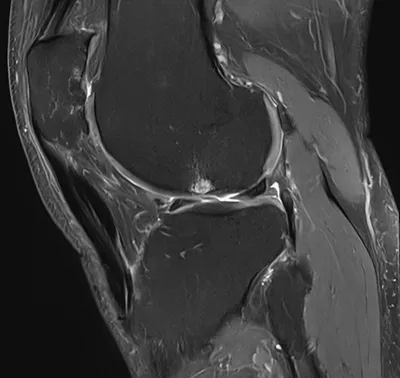

Posterior meniscocapsular ligament injury

MRIKneeSagittal+2

4/23/2026